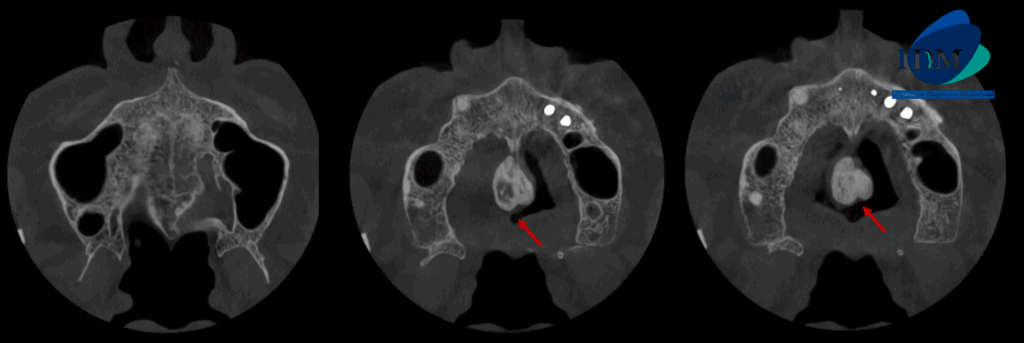

A la evaluación de la tomografía volumétrica (cone beam) bimaxilar en los cortes axiales (Figura 2) y transaxiales (Figura 3) se observa imagen hiperdensa de densidad ósea y forma bilobular localizada en en zona de paladar duro a nivel de línea media

CORTES AXIALES

CORTES SAGITALES

CORTES TANGENCIALES